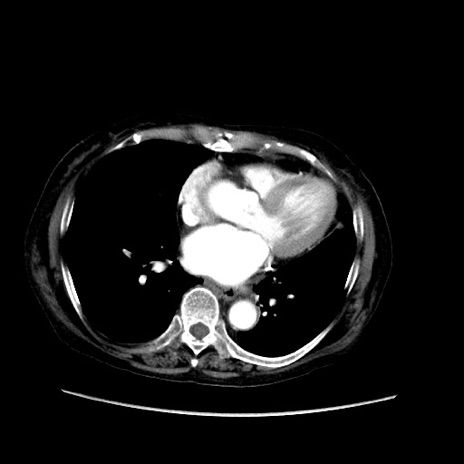

矢状断像

【症例】80歳代 女性

【主訴】腹部膨満感

【現病歴】他院にて肝硬変にてフォロー中。1週間前から便秘、腹部膨満感、臍部腫瘤あり受診となる。

【既往歴】肝硬変

【身体所見】腹部膨隆あり、皮膚変化なし、疼痛なし。

【データ】WBC 4600、CRP 0.25